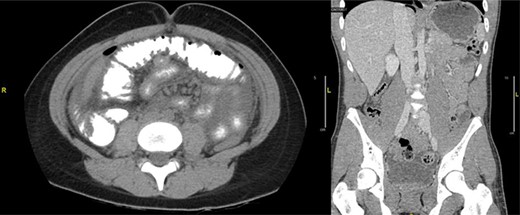

The patient was taken to the operating room for diagnostic laparoscopy. A 4-mm perforated duodenal ulcer by the pylorus with leaking bile was found and repaired with an omental patch. On postoperative Day (POD) 3, an upper gastrointestinal study was done, which showed no signs of obstruction or leak (Fig. 2). Serum gastrin levels were reported normal. On POD 4, he was started on a diet. He tested positive for Helicobacter pylori and was therefore treated with eradication triple therapy (proton pump inhibitor, amoxicillin and clarithromycin). The patient recovered uneventfully and was discharged home on POD 7, and was symptoms free at follow-up.

Upper gastrointestinal series (a)/small bowel follow-through (b): normal stomach demonstrated. Normal duodenum and proximal jejunal loops. No contrast extravasation identified. Oral contrast in the distribution of stomach, duodenum and proximal jejunal loops with no evidence for extravasation.